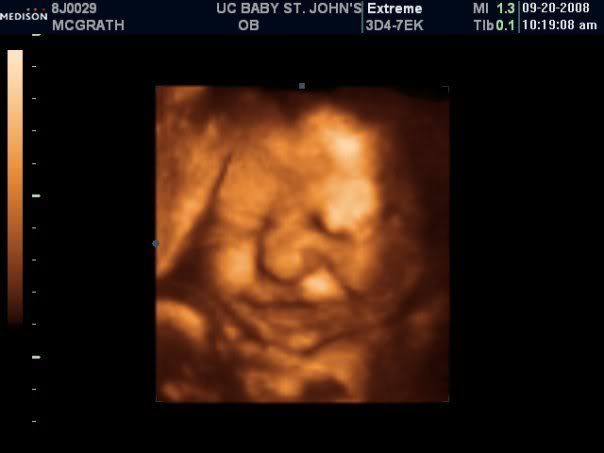

I had the uc one done here last week... I couldn't wait I was further along then they liked... but we got pretty good pictures and they also confirmed that she was def. a she! Posted Image[/IMG] Edited by Vanessa*momto2*, Sep 25 2008, 09:51 PM.

She's beautiful! She looks like she's smiling!!!! |

That's a great shot! I agree with Joe totally looks like she is smiling. |